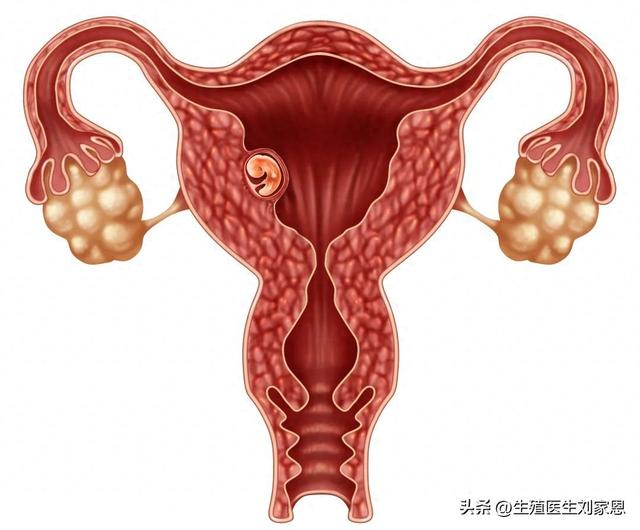

宫外孕隐患当受精卵在子宫以外的部位,如输卵管、卵巢等地方着床时,因着床部位的营养供应不足,滋养层细胞难以正常发挥功能,分泌的HCG量受限,导致HCG翻倍不明显。宫外孕不仅会严重威胁女性的生育能力,若不及时处理,还可能引发大出血,危及生命。